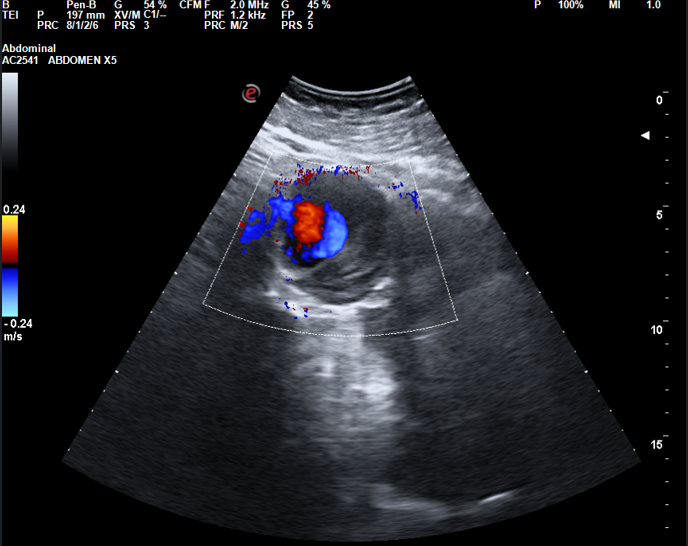

Ecografía abdominal: Hígado de tamaño y ecogenicidad normal, sin dilatación de vía biliar. Vesícula de pared fina con litiasis única en su interior. Páncreas de aspecto normal. Ambos riñones de tamaño normal, con buena diferenciación corticomedular, sin dilatación de vía urinaria ni presencia de litiasis. Bazo de tamaño y ecogenicidad normal. En el rastreo de abdomen inferior se descubre incidentalmente aorta abdominal con aumento de su diámetro (5,6 x 5,3 cm), se aprecia imagen de engrosamiento de pared compatible con trombo intramural y luz permeable de 1,7 x 1,9 cm.